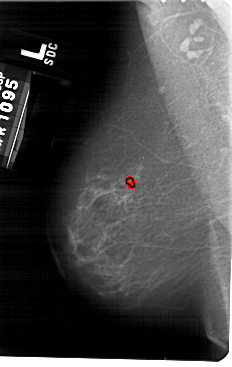

A_1479_1.LEFT_MLO

LEFT_MLO LINES 5491 PIXELS_PER_LINE 3466 BITS_PER_PIXEL 12 RESOLUTION 43.5 OVERLAY

FILE: A_1479_1.LEFT_MLO.OVERLAY

TOTAL_ABNORMALITIES 1

ABNORMALITY 1

LESION_TYPE CALCIFICATION TYPE PLEOMORPHIC DISTRIBUTION CLUSTERED

ASSESSMENT 4

SUBTLETY 2

PATHOLOGY BENIGN

TOTAL_OUTLINES 1

BOUNDARY